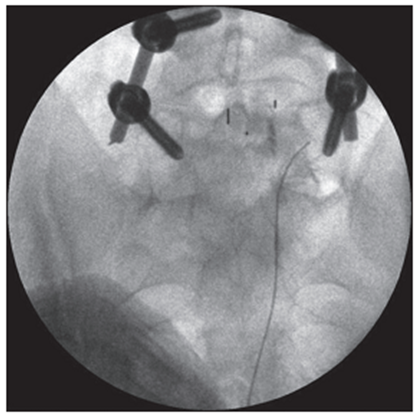

Figure 2. Lateral intraoperative radiograph of the lumbar spine. The tip of the puncture needle is located in the upper outer quadrant of the intervertebral foramen LIV-V |